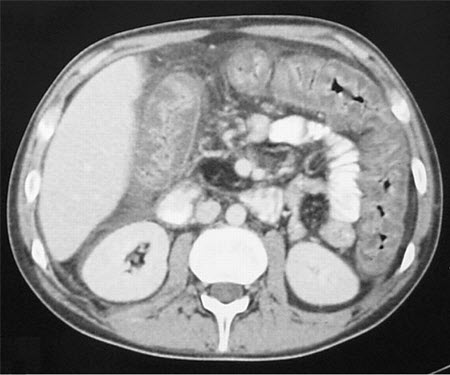

Doença de Crohn: Tomografia computadorizada (TC) mostrando espessamento do íleo terminal em um paciente com exacerbação da doença de Crohn

Fornecido pelo Dr. Wissam Bleibel, Dr. Bishal Mainali, Dr. Chandrashekhar Thukral e Dr. Mark A. Peppercorn